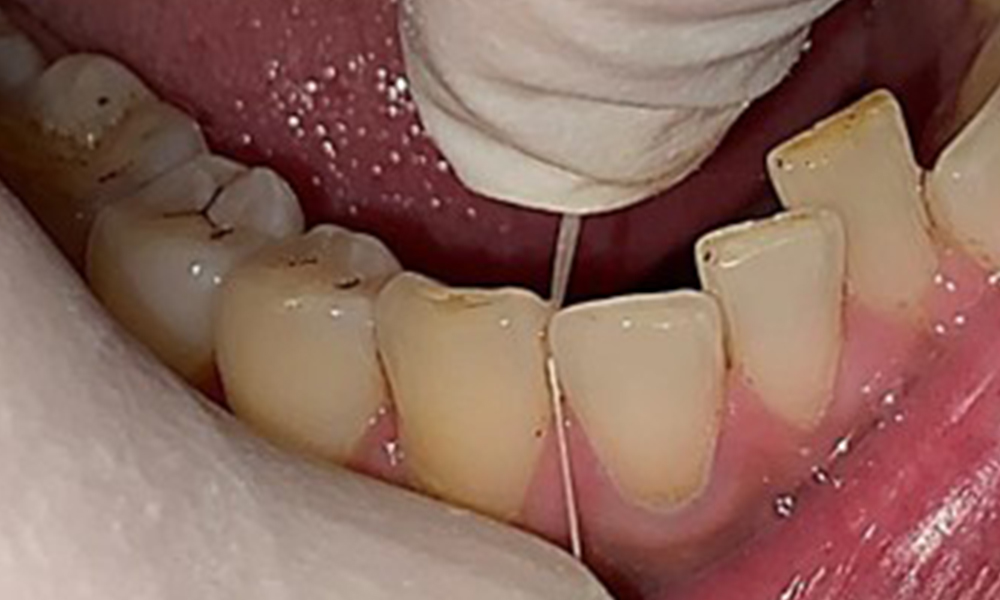

Instruction and motivation are important components of these appointments. Good home-based intraoral hygiene behaviour and understanding are important for patients. Plaque accumulation is particularly evident in the cervical regions (Fig. 8).

The arrows indicate plaque accumulations in the cervical region

Fig. 8: The arrows indicate plaque accumulations in the cervical region, © Dr R. Krapf

These must be discussed with the patient, and improvements to the teeth-brushing technique must be practised. A soft toothbrush attachment is recommended for home-based intraoral hygiene due to the presence of erosions and attritions.